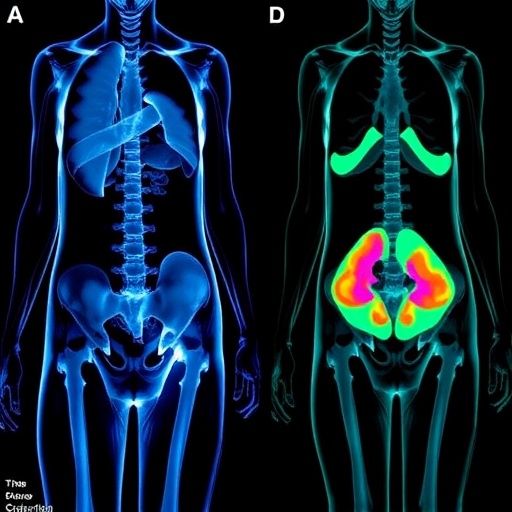

PET Imaging Reveals Whole-Body Metabolic Shifts Following Bariatric Surgery

In a groundbreaking advancement in metabolic medicine, researchers at the Medical University of Vienna have utilized an innovative whole-body positron...